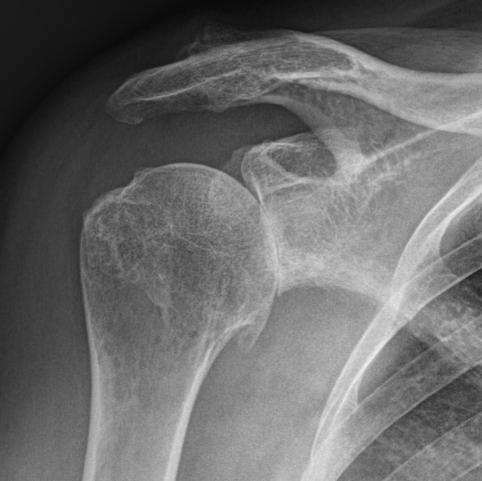

Les pathologies liées à l’épaule

Selon la pathologie affectant l'articulation de l'épaule, les options thérapeutiques, qu'elles soient médicales ou chirurgicales, seront abordées lors de la consultation, en tenant compte de vos examens médicaux et de vos attentes fonctionnelles.